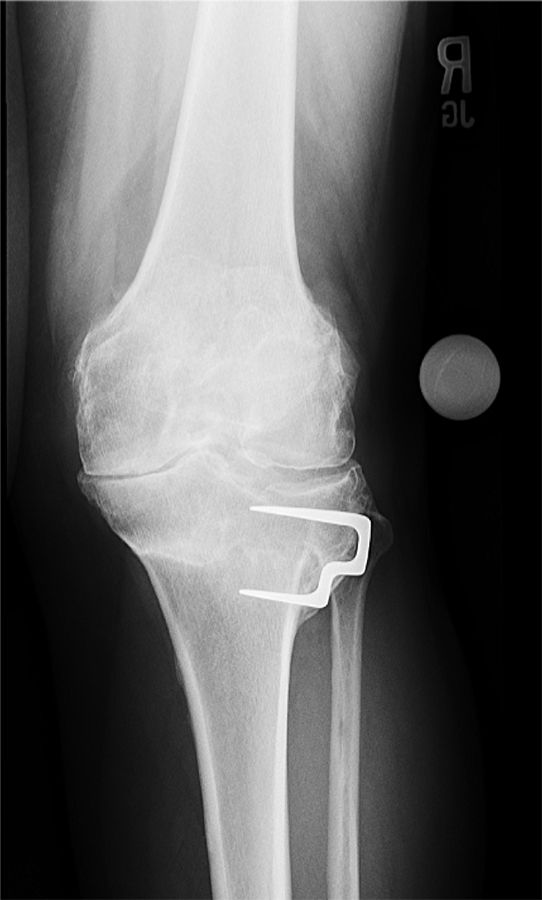

Often the first question is whether or not to remove preexisting hardware at the time of surgery or two-stage prior to knee replacement. Although there have been reports of positive cultures when evaluating removed hardware, I don’t think that prior hardware always needs to be removed before attempting a total knee replacement. Medial hardware on the proximal tibia or distal femur can usually be removed without difficulty through a standard medial parapatellar approach at the time of total knee replacement (Figure 6a, b).

I usually take a careful history of prior infections, open fracture and delayed wound healing after the initial open reduction and internal fixation. I have a low threshold to aspirate knees prior to implantation to exclude the remote possibility of a chronic infection or change my plan to a two-stage procedure if the removed hardware looks suspicious. An MRI imaging might help to detect evidence of osteomyelitis. In the presence of lateral hardware, I usually prefer to remove the hardware in a two-stage fashion. I don’t feel comfortable having a second incision around the knee at the time of a total knee replacement (Figure 7a, b).

At times I might retain hardware and proceed directly to a total knee arthroplasty without removal of the hardware (Figure 8a, b).